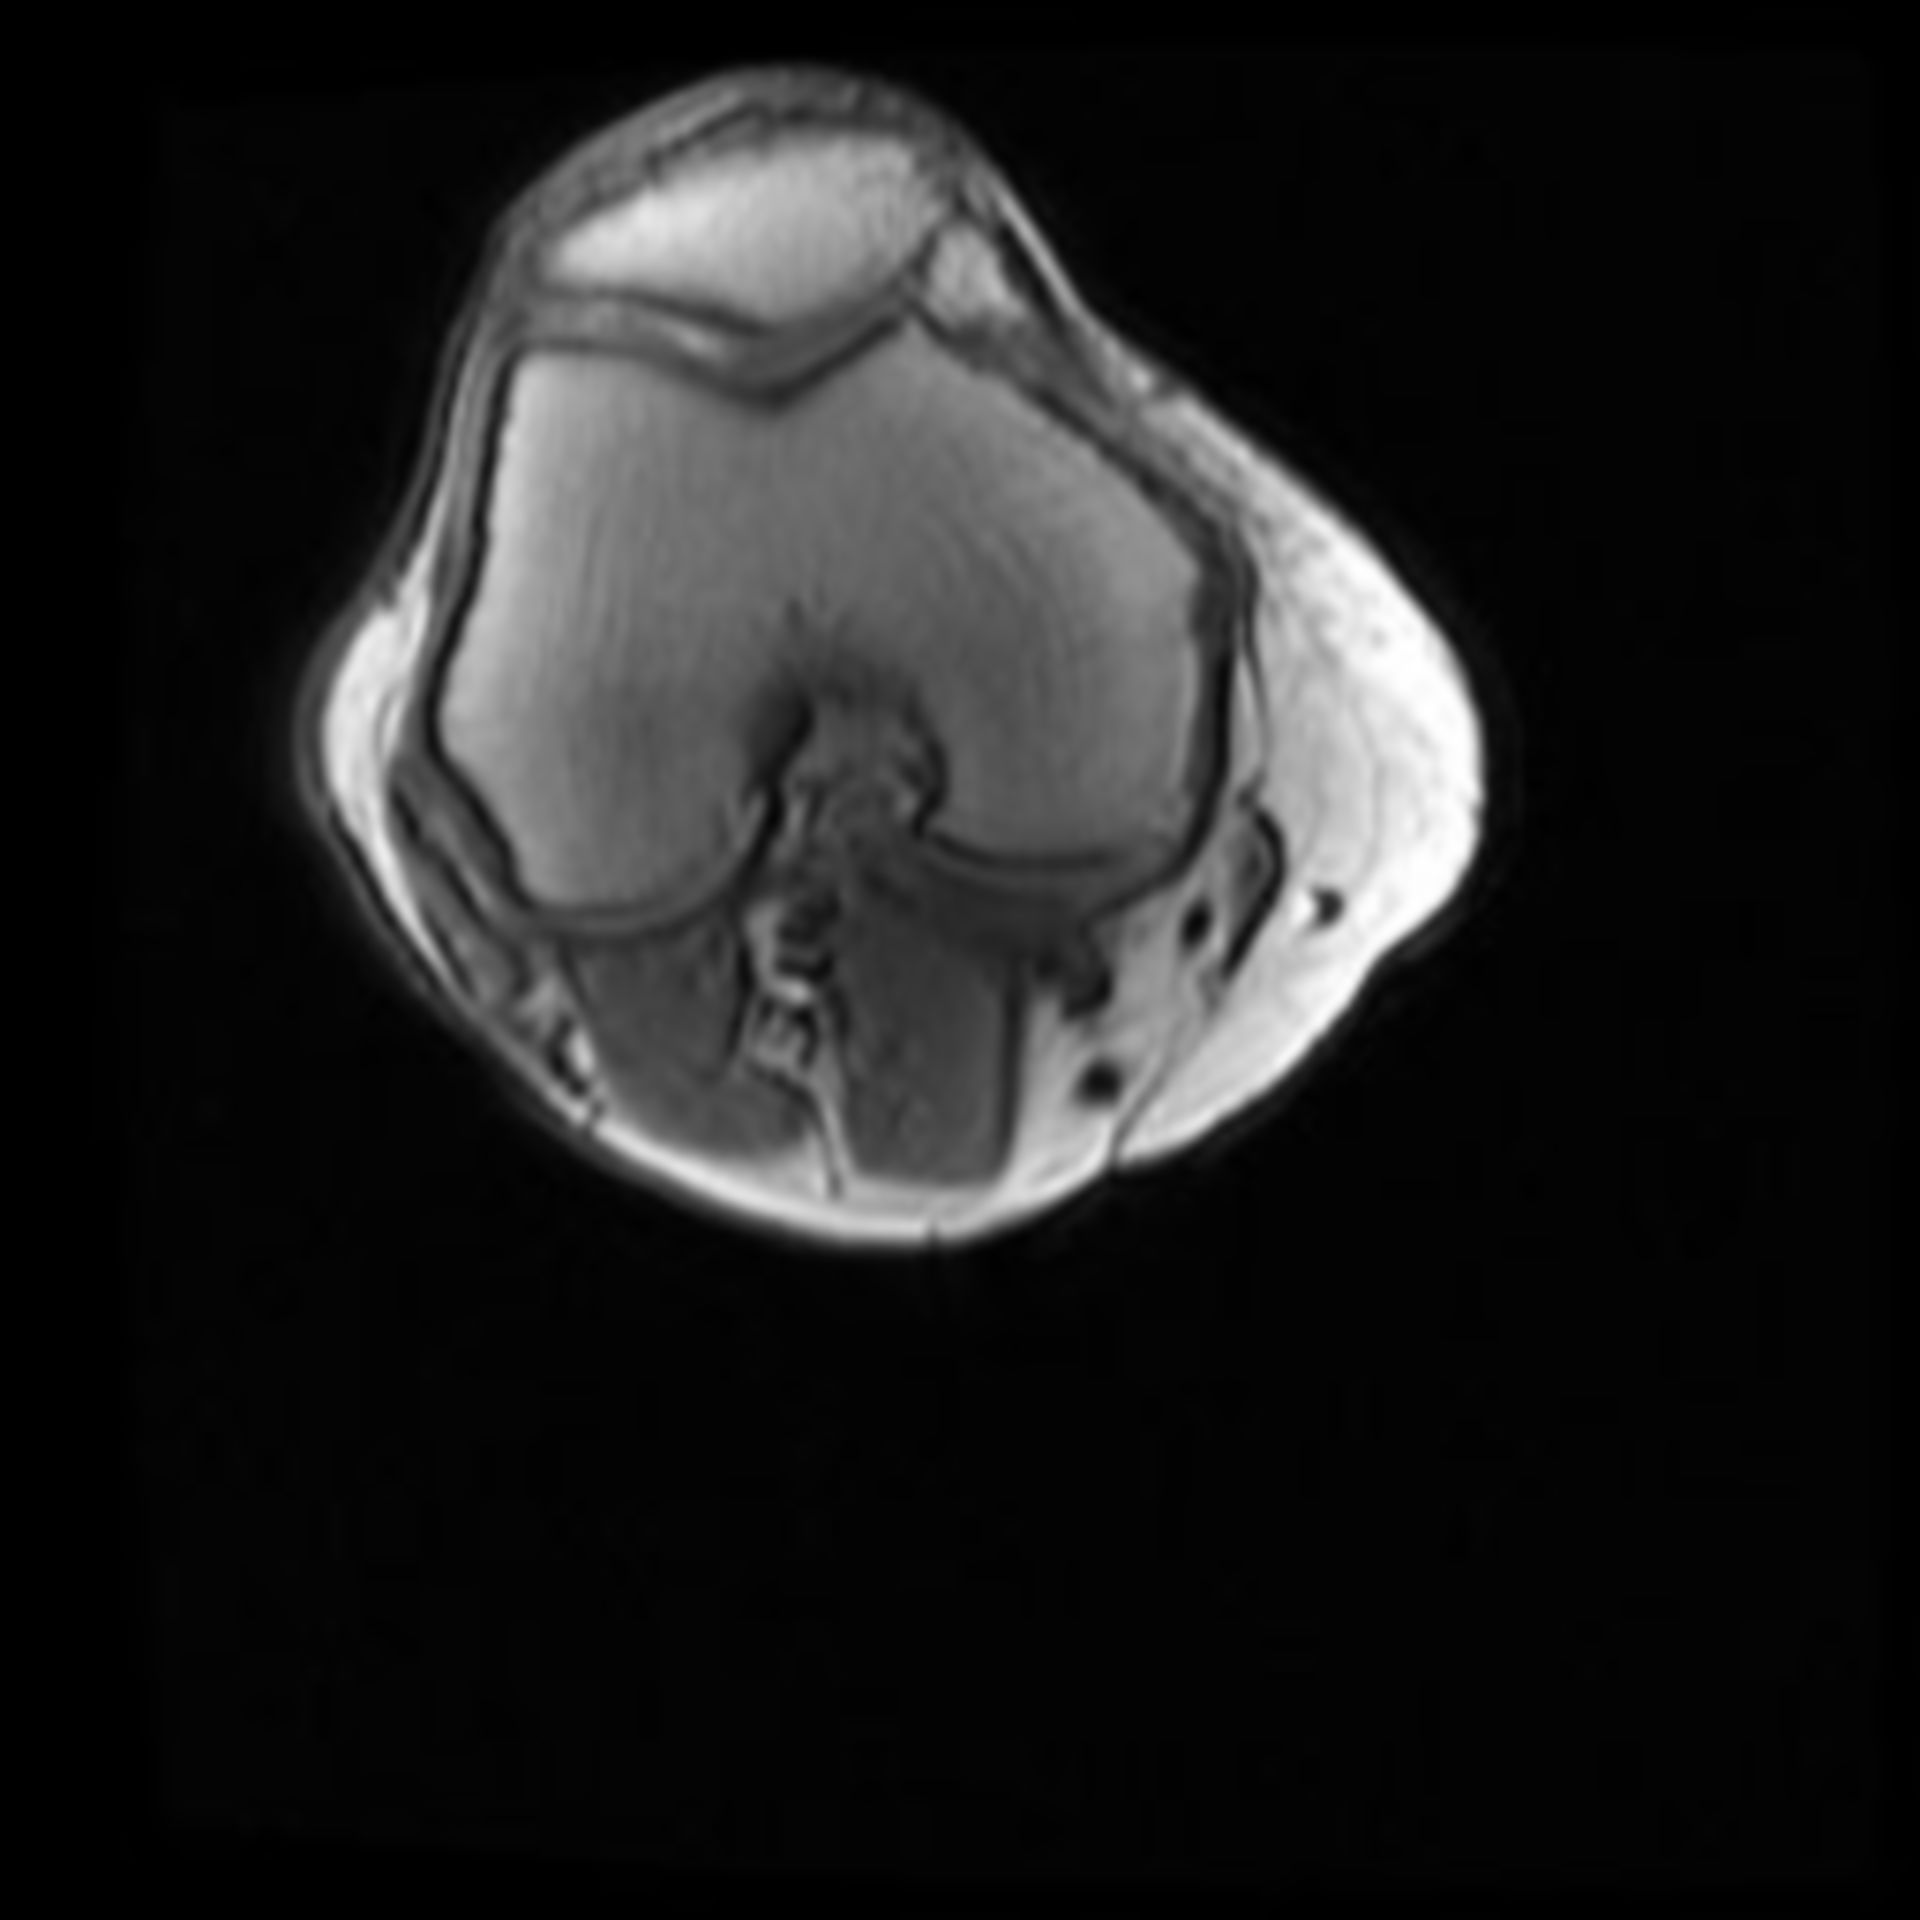

MRT Knie – DocCheck MRT Niere3 – DocCheck

MRT: Knie – DocCheck MRT in der Krebsmedizin

MRT Knie links HWS ARTHROSE, MRT Stockfotografie – Alamy

MRT Knie links MRT der akuten MS Stockfotografie – Alamy

MRT Knie links Mrt Bilder Schulter Sehnenriss – Captions Blog

MRT: Knie – DocCheck MRT Schädel – DocCheck

MRT Knie linksสถานีMRTแทบแตก? คนเยอะมาก รถไฟไทย🇹🇭พามาดูความลึกความยาวสถานีสามยอดไทยสร้างได้ไง!ความลึกเท่าตึก3ชั้น😯